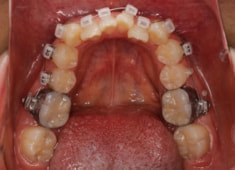

左上3番埋伏歯

治療法:フルパッシブブラケット:T21

治療開始から11ヶ月後